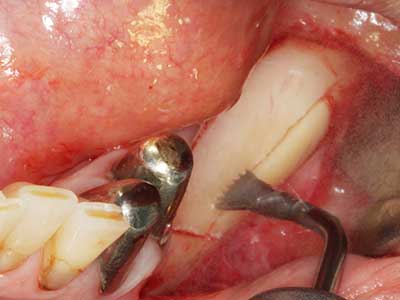

Aplicación: Obtención de hueso autógeno

Los injertos de hueso autógeno se utilizan en forma de bloques, escudillas, anillos y también se combinan con materiales de reemplazo óseo como virutas. Si el sitio del implante se prepara al mismo tiempo que el aumento, hay diversos sistemas de filtrado óseo que han demostrado su eficacia para la recopilación de las virutas óseas que se producen. Como alternativa, el sitio del implante se puede preparar usando un dispositivo de baja velocidad sin irrigación y si no se inserta ningún implante, es posible obtener virutas óseas de la periferia utilizando las rasquetas adecuadas. Esto también es posible aplicando cirugía piezoeléctrica con piezas especiales, y así se demostró en un estudio específico en el que se realizó una comparación directa con las virutas obtenidas con fresas redondas, ya que las virutas obtenidas con el método piezoeléctrico presentaron una mejor calidad (Chiriac, Herten et al. 2005).

En la extracción de bloques óseos la piezocirugía también presenta ventajas adicionales: Además de la alta precisión en la osteotomía que ya se ha descrito antes, se ha comprobado que el uso de los delgados insertos de sierra resulta especialmente cuidadosas con el hueso. Frente a esto, sobre todo cuando se usan las fresas de Lindemann, cabe esperar pérdidas en la extracción significativamente más altas debido al mayor grosor de la parte frontal del cabezal (Lakshmiganthan, Gokulanathan et al. 2012). La separación basal que se necesita en particular en los injertos de bloque extraídos de forma retromolar se ve facilitada mediante sierras perpendiculares especialmente previstas a tal fin, lo que permite considerar que la cirugía piezoeléctrica es un procedimiento preciso y seguro para la obtención de bloques de hueso en el área retromolar (Happe 2007) (fig. 1-12).